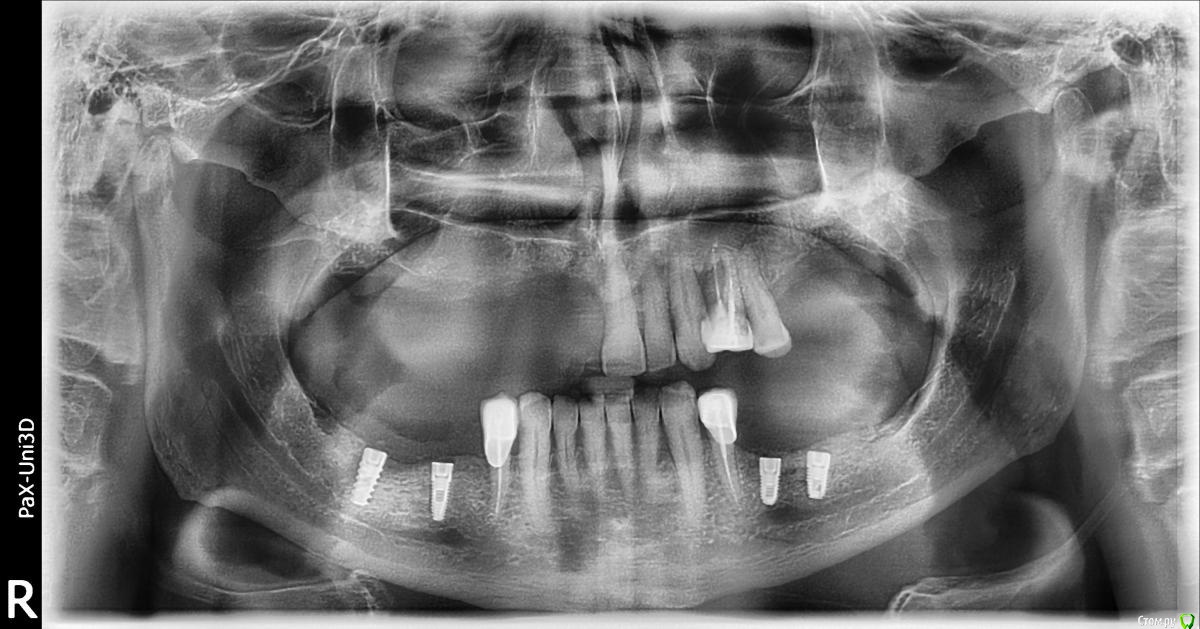

Kostoprav Опубликовано 1 августа, 2016 Поделиться Опубликовано 1 августа, 2016 что бы вы сделали в данной ситуации уважаемые коллеги? был синус и титановая сетка во фронте но увы все прокисло ((( 1 Ссылка на комментарий

Kostoprav Опубликовано 2 августа, 2016 Автор Поделиться Опубликовано 2 августа, 2016 Всё вычистить, подождать заживление и повторить.это кт уже после чистки, а повторить снова титановой сеткой?думаю снова сетка здесь не прокатит( Ссылка на комментарий

Kostoprav Опубликовано 3 августа, 2016 Автор Поделиться Опубликовано 3 августа, 2016 скисло через 3 мес, до этого все было идеально!но меня больше беспокоит вопрос что теперь с этим делать, там теперь кости особенно во фронте почти нет.какую технику использовать? Ссылка на комментарий

Fibez Опубликовано 3 августа, 2016 Поделиться Опубликовано 3 августа, 2016 Меня не удивляет что резорбировался графт под сеткой. Но где тут графт в пазухе? Что там было с синуслифтингом? Ссылка на комментарий

Kostoprav Опубликовано 3 августа, 2016 Автор Поделиться Опубликовано 3 августа, 2016 Меня не удивляет что резорбировался графт под сеткой. Но где тут графт в пазухе? Что там было с синуслифтингомначалось все как раз из синуса. пазуха разделена перегородкой, я поднял дно только в передней камере Ссылка на комментарий

Kostoprav Опубликовано 9 августа, 2016 Автор Поделиться Опубликовано 9 августа, 2016 Мороз Владимир Михайлович ОПТГ.bmp Ссылка на комментарий

kriokov Опубликовано 10 августа, 2016 Поделиться Опубликовано 10 августа, 2016 это , то, что есть сейчас? Ссылка на комментарий

Kostoprav Опубликовано 10 августа, 2016 Автор Поделиться Опубликовано 10 августа, 2016 да Ссылка на комментарий